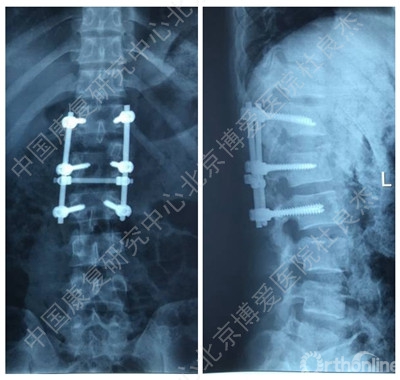

手术后辅助检查

3、胸12椎弓根钉断裂

1.手术失败的原因?

2.下一步治疗方案?

柳申鹏 #1胸腰段椎体骨折脱位出现断钉原因:1.此处骨折脱位除椎体骨折外,附件及韧带等软组织损伤严重。从解刨上看3种因素决定此处是应力集中地。需固定到伤椎上下各2个椎体。2.从影像学可知,胸12腰1似乎过度撑开了。3.从影像学可知,极度不稳,应融合胸12腰1。下一步:去除断钉,延长上方固定到胸10或11并做后路截骨椎间隙植骨。或前路椎间隙植骨融合内固定

沈晓震 #2AO分型,C3型骨折,极度不稳。胸腰段骨折,根据Load–sharimg评分,大于7分,且伴有后方结构破坏,单纯的后路短节段固定稳定性肯定是不行的,内固定失效的可能性较大。建议后方长节段固定+前方植骨融合内固定。